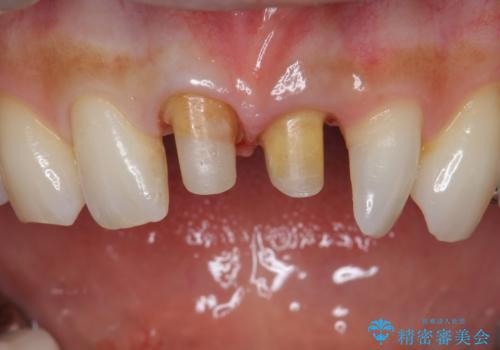

- 前歯の変色とガタつきがきになるとのことで来院されました。

矯正治療の希望はなかったため、セラミッククラウンで被せて治療していくことになりました。

元々根管治療がされていたにも関わらず被せ物が作られておらず、このままではどんどん変色が進んでいってしまう状態でした。

歯をある程度削ることにはなりますが、被せ物にすることで歯の変色を隠し短期間でキレイな口元に仕上げることができました。